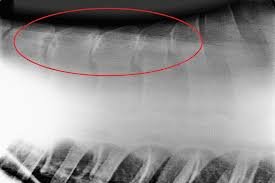

Kissing spine je stav, kdy jsou trnové výběžky obratlů příliš blízko u sebe a při extenzi (prohnutí) páteře se o sebe “třou” – v důsledku toho vznikají léze na trnových výběžcích. Nejčastěji vznikají problémy v oblasti mezi 12. až 18. hrudním obratlem nebo v bederní páteři. Diagnóza je stanovena veterinářem na základě klinických příznaků a rentgenologického nálezu.

Toto je RTG snímek páteře koně, který trpěl bolestmi zad, nicméně i přesto byl jezditelný, jen vykazoval diskomfort pod sedlem. Žlutě jsou zvýrazněna místa, kde pozorujeme důsledek kontaktu trnových výběžků obratlů k sobě navzájem. Vidíte, že postižená oblast je poměrně rozsáhlá.

Často se ovšem stává, že nález na rentgenu nekoreluje s klinickými příznaky – tedy v některých případech je kissing spine jen náhodným nálezem a kůň nevykazuje bolestivost zad, někdy jsou koně hodně bolaví a na rentgenu je jen minimální nález.